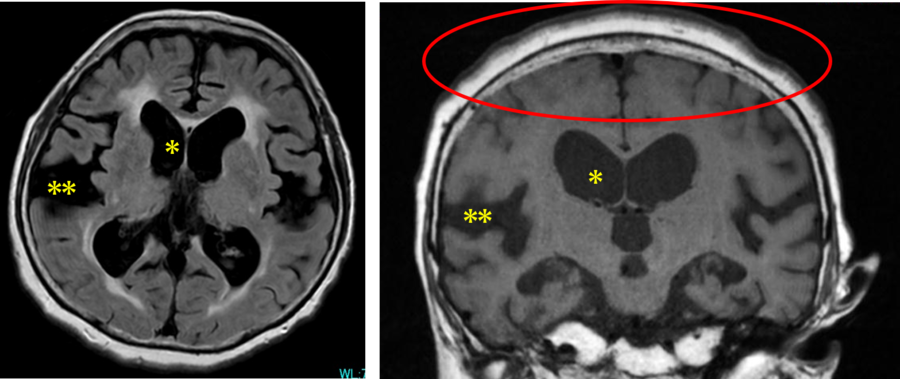

典型的な特発性正常圧水頭症の画像所見 (MRI 左:軸位断 右:冠状断)

* 脳室拡大

** シルビウス裂開大

〇 高位円蓋部脳溝狭小化所見